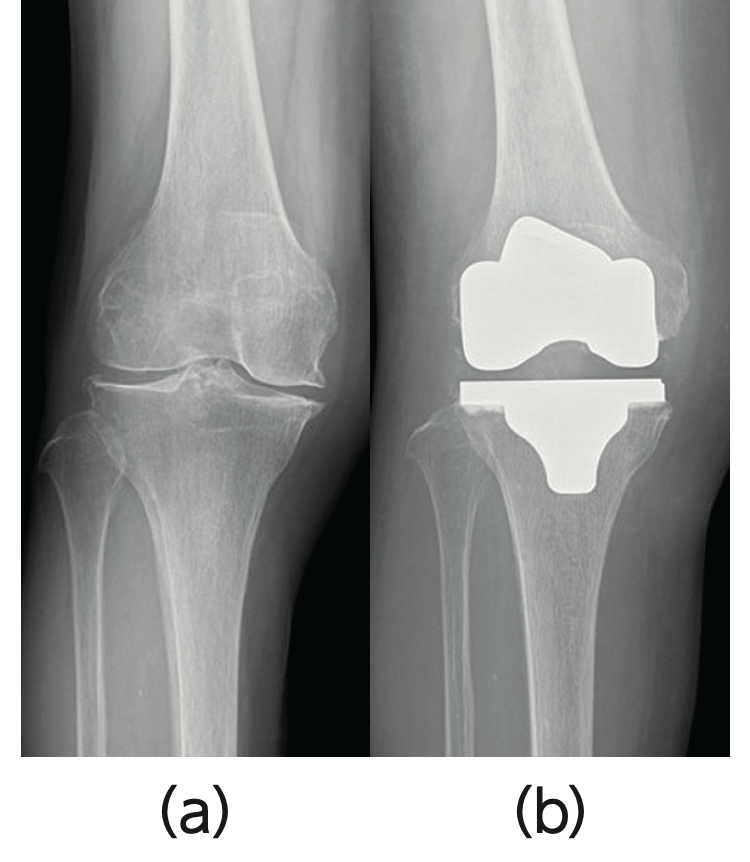

- ・人工膝関節全置換術(図3)

- 進行した変形例でも痛みを取り除き、膝の曲げ伸ばしや膝の安定性の再獲得に優れており、わが国では年間約10万件行われています。当院では、2021年4月に人工関節手術にロボティックテクノロジーを導入し、これまで以上に高精度な手術を施行しています(詳しくは(「高精度な操作による人工膝関節置換術」))。

変形性膝関節症が進行し、保存療法で痛みがコントロールできない症例(a)やさらに変形が著明な症例では、人工膝関節全置換術を施行します(b)